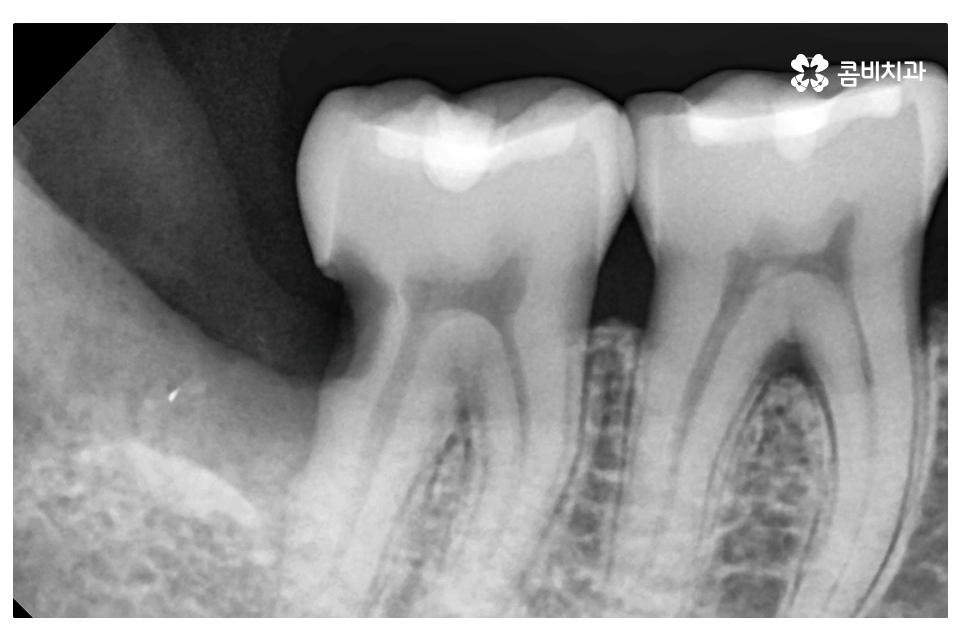

오늘 보여드린 환자분의 케이스는 사랑니로 인해 어금니에도

충치가 발생한 사례로 이처럼 치아 사이에 충치가 발생하면

치아의 하단부, 안쪽에 손상이 발생하기 때문에

어금니 신경치료를 하게 되는 경우로 이어질 수 있어요.

엑스레이 사진에서 보시는 것처럼 사랑니로 인해 어금니 옆 부분에

충치가 발생되었고 사랑니 발치 후 어금니 신경치료를 하여

자연치아의 손상이 커진 케이스라고 할 수 있는데요